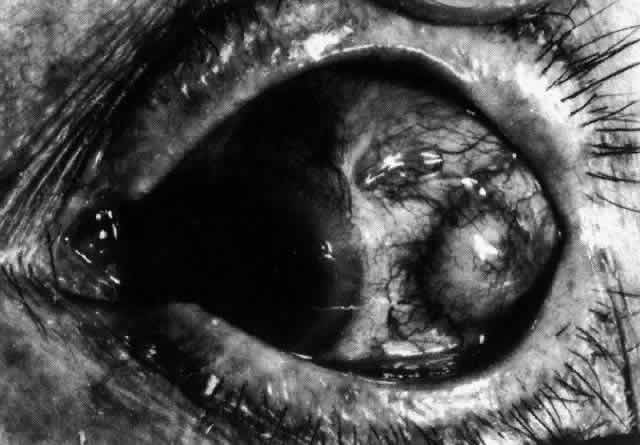

Simple and nodular episcleritis differ in their clinical courses, but in both the edema and infiltration are entirely within the episcleral tissues. The sclera is not involved. The maximum congestion is in the superficial episcleral network, with some slight congestion of the conjunctival vessels and deep episcleral vessels (Fig. 10). The intraocular structures are not involved in either variety, nor is the visual acuity affected. Anterior segment fluorescein angiography reveals a normal vascular pattern but a very rapid flow rate, with the whole transit of the dye being completed within 2 or 3 seconds (Figs. 11 and 12).

Fig. 10. Maximum congestion in the superficial vascular plexus in episcleritis. The conjunctival and deep episcleral networks are separated from the deep plexus by edema and infiltration in the episcleral tissue. (Watson PG, Hayreh S, Awdry P: Episcleritis and scleritis. Br J Ophthalmol 52(3):278–279, 1968)

The redness of simple episcleritis may be intense, varying from a fiery-red or a brick-red discoloration to a mild red flush, but it does not have the bluish tinge that is seen in scleritis. The distribution is usually sectorial but can involve the whole anterior segment of the globe. The episcleral vessels are engorged but retain their normal radial position and architecture (Figs. 13 and 14; Color Plate 1A). In simple episcleritis, there is a diffuse edema of the episcleral tissues. These tissues are sometimes infiltrated with gray deposits that appear yellow in red-free light. Surprisingly, the eye is rarely tender to the touch.

Fig. 13. Infiltration of the episclera in which the superficial episcleral vessels show maximal congestion. Conjunctival vessels are slightly congested, as is the deep episcleral plexus, whose irregular criss-cross pattern can be seen deep to the radially arranged superficial episcleral plexus.